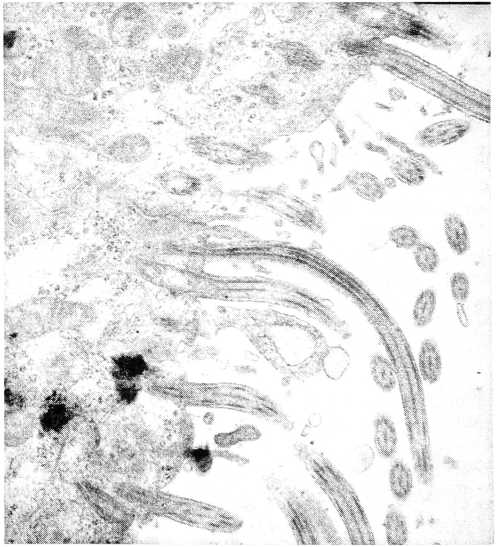

Рис. 8. Гидросальпинкс.

На поперечных срезах ресничек обнаруживается нетипичная организация микротрубочек (1): отсутствие одной пары периферических микротрубочек, дезорганизация микротрубочек в виде «разбегания» в цитоплазме реснички, что косвенно свидетельствует о нарушении белков, организующих их, — динеиновых ручек, нексиновых мостиков и радиальных спиц. Электронограмма, увеличение × 50000